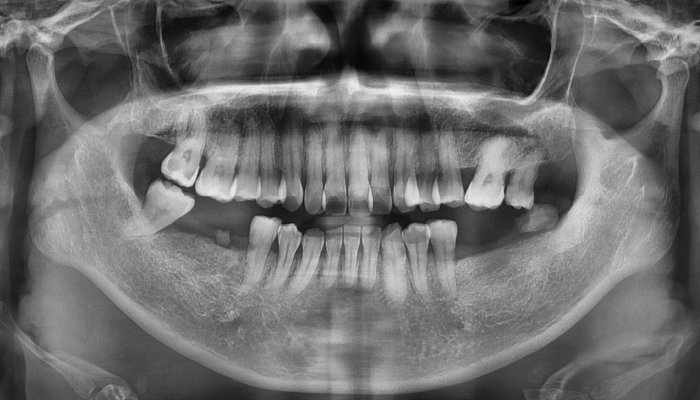

뼈이식 임플란트 전후 사례

• 식립 전

식립 후